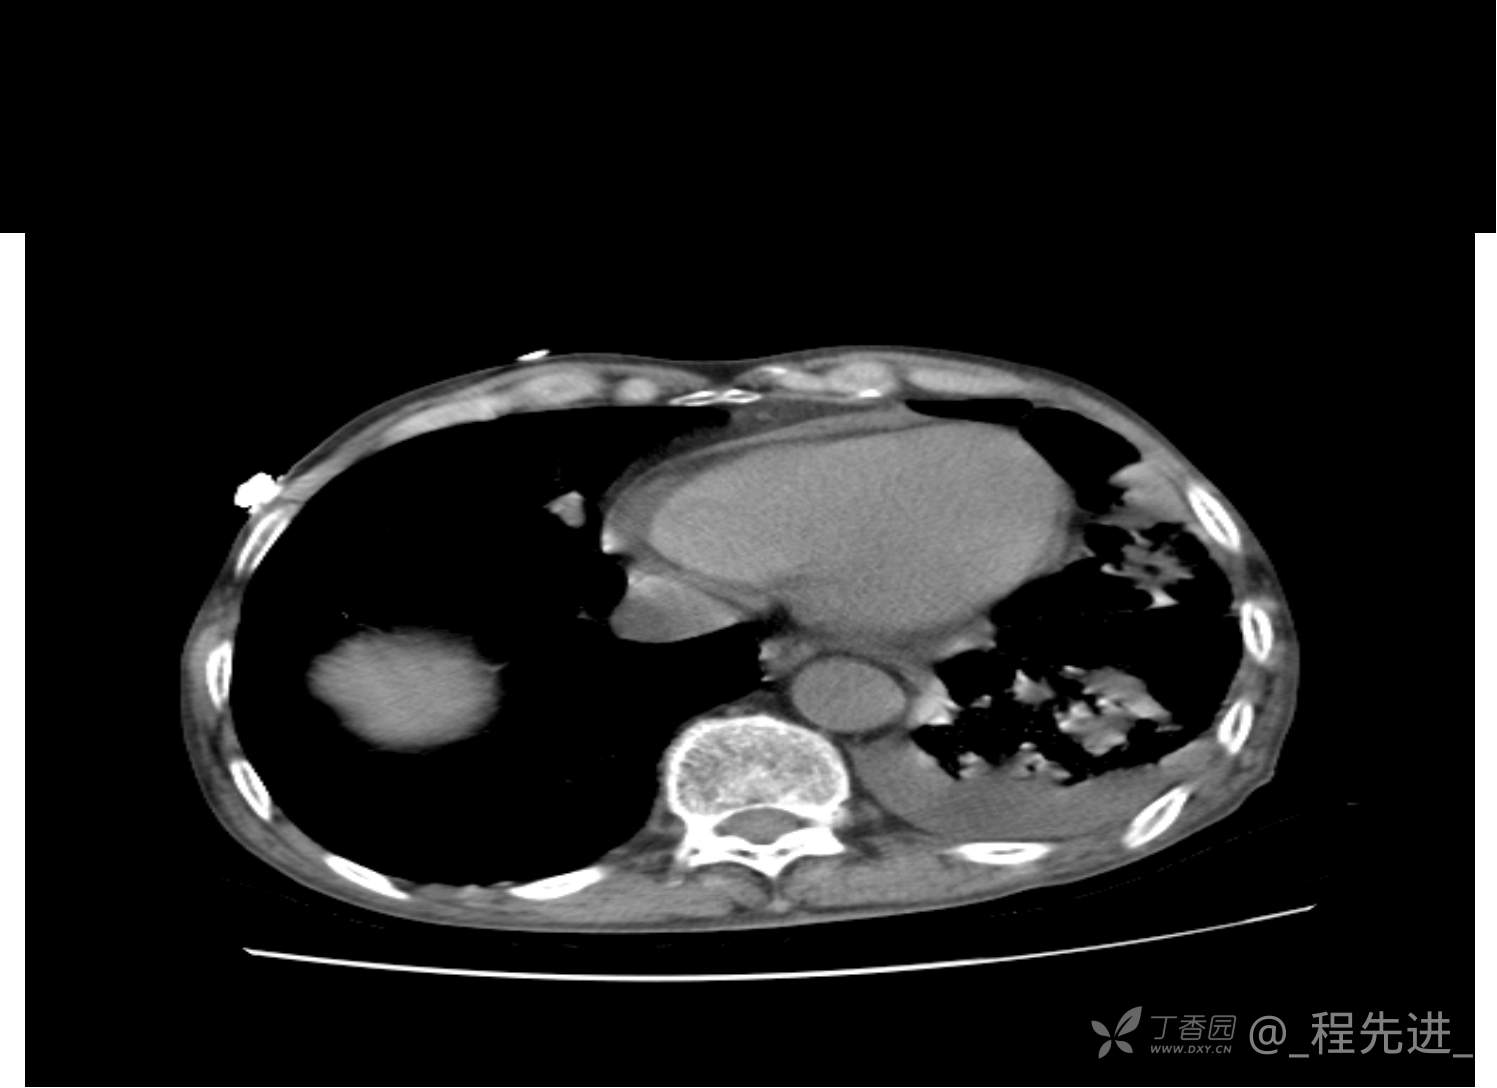

患者性别:男

患者年龄:81岁

简要病史:反复咳嗽、咳痰20余年,加重1周。两肺呼吸音低,可闻及散在干湿啰音。